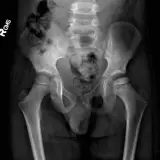

Over 2,100 interactive radiology cases, curated by radiologists for your level of training. Scroll, window, and view cases full screen โ€” just like on PACS. Click linked findings in each writeup to jump straight to them on the image. Cases include sample reports, a focused discussion section, original illustrations, and videos.

Casi completamente interattivi con gli strumenti che ti aspetti su un PACS: scroll, windowing, zoom, pan, misurazioni, ROI e modalitร  a schermo intero.

Annotazioni dettagliate evidenziano i reperti chiave direttamente sui casi. Clicca sui reperti collegati nella descrizione del caso per saltare alla loro esatta posizione sullo scan.